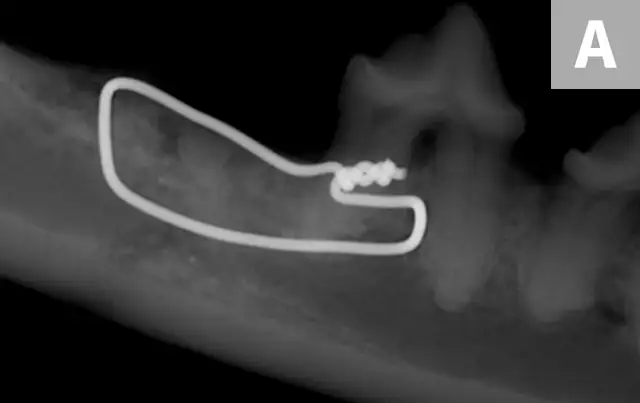

A regional anesthetic agent (0.5% bupivacaine [0.2 mL]) was injected where the mandibular nerve enters the mandibular canal (inferior alveolar nerve block). The affected teeth were surgically extracted to minimize distraction of the bones, the area was gently debrided, and each mandible was stabilized with a single intraosseous wire; the oral soft tissues were sutured in a simple interrupted pattern with 5–0 poliglecaprone-25 to completely cover the bone (Figure 3). This provided sufficient reduction of the fractures and adequate stability.

The patient was presented 7 weeks later for a recheck oral examination under general anesthesia (performed in the same manner as previously). Dental radiographs demonstrated healing of the fractures (Figure 4). The interfragmentary wires were removed via an intraoral approach, and postoperative intraoral radiographs were obtained to confirm adequate healing (Figure 5). The patient recovered uneventfully.

FIGURE 3A

Postoperative intraoral dental radiographs of the right (A) and left (B) mandible following reduction and fixation with a single intraosseous wire on each side.